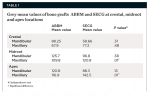

A total of 20 bone graft sites were analyzed radiographically with ImageJ software to obtain the grey values at three locations (apex, midroot, and crest) within the grafted socket area after 6 months of healing. The estimated mean grey values of the crestal, midroot, and apex areas of the mandible and crestal area of the maxilla were not significantly different between the two materials (P = .31, .38, .13, and .48, respectively). For the maxillary arch, the estimated mean grey values of the midroot and apex with ABBM were significantly lower than the estimated mean grey value of the SECG material (P = .01) (Table 1).